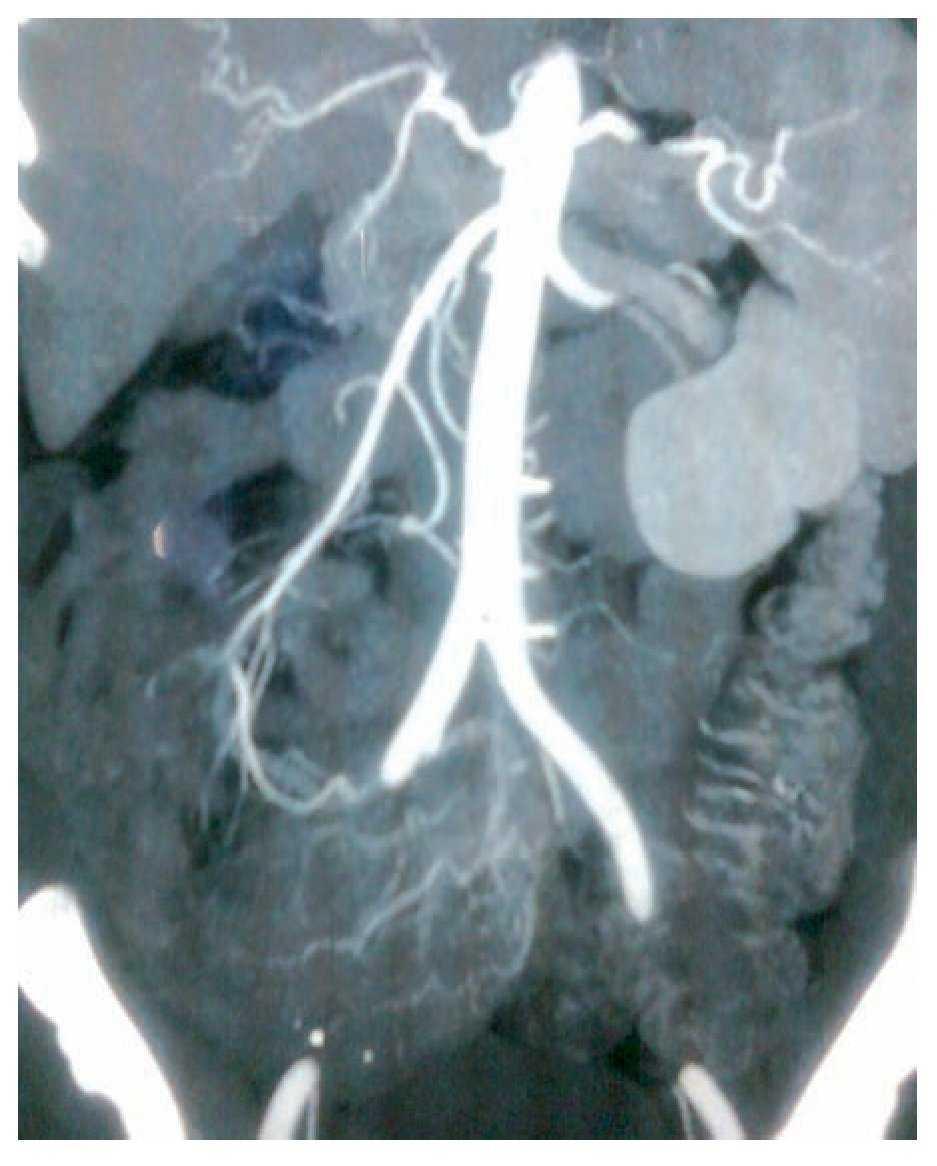

Mujer de 47 años, diabética e hipertensa de larga evolución, con antecedente de nefrectomía derecha por donación cinco años antes. Su padecimiento se inició a fines de 2008 con presencia de evacuaciones hematoquézicas y melena, por lo que requirió múltiples transfusiones. La endoscopia alta y colonoscopia no detectaron el sitio de hemorragia. En agosto de 2009 presentó choque hipovolémico secunadario a hematoquezia (hemoglobina de 3.5 g/dL) que requirió de transfusión de siete paquetes globulares. Se realizaron nuevamente endoscopia alta y colonoscopia que no detectaron en sitio de hemorragia. El gammagrama con eritrocitos marcados mostró concentración anormal del radioisótopo en la flexura hepática. Una enteroscopia no mostró sangrado evidente. Se practicó una angiografía selectiva de arteria mesentérica superior (AMS) en fase arterial (Figura 1), que mostró vasos de neoformación tortuosos e irregulares a nivel de íleon, sin retorno venoso temprano. La angio-tomografía computarizada (angioTC) con reconstrucción coronal y proyección de máxima intensidad (Figura 2), detectó una imagen hipodensa, con vasos tortuosos de neoformación que nacían de la AMS. La angioTC en 3D (Figura 3) reveló múltiples vasos de neoformación dependientes de la AMS localizados en íleon que demuestran una tumoración con gran vascularidad. Se realizó laparotomía exploradora encontrando un tumor a 90 cm de la válvula ileocecal (Figura 4). El análisis histopatológico determinó tumor estromal de alto grado con bordes quirúrgicos libres de lesión, con inmunohistoquímica para CD117 (Figura 5) y S100 positivos.

¿ Figura 3. AngioTC 3D. Se evidencian vasos de neoformación dependientes de la AMS.